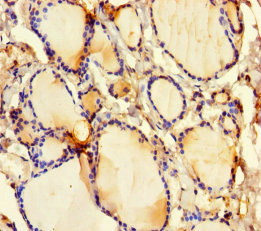

Immunohistochemistry of paraffin-embedded human thyroid tissue using CSB-PA006766LA01HU at dilution of 1:100

Immunohistochemistry of paraffin-embedded human breast cancer using CSB-PA006766LA01HU at dilution of 1:100

| CSB-PA006766LA01HU | GSDME Antibody | Human | ELISA, IHC, IF |